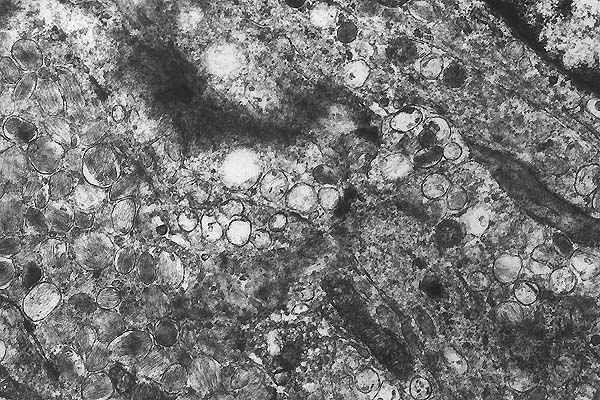

- Case 19-3. Rat A, 6100x

This electron micrograph contains portions of multiple, interdigitating

spindle cells, 2 with visible nuclei. The cells have ovoid nuclei

with dispersed chromatin and abundant cytoplasmic organelles,

and are joined by desmosomes. The most prominent organelles are

multiple, ovoid, approximately 0.3 x1.0 (single membrane-bound

structures, with multiple internal membranous filaments arranged

in parallel to the long axis [premelanosomes (stage II melanosomes)].

Other cytoplasmic organelles are present in low number and include

rough endoplasmic reticulum (RER), mitochondria and multiple

membrane-bound vacuoles with scant contents (most likely dilated

RER).